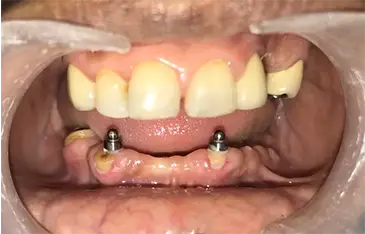

Case 4: Maxillary Hybrid Denture